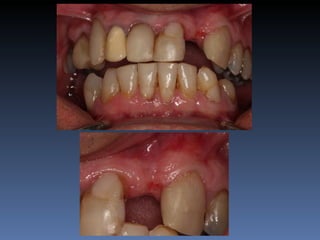

BOX 4

Maurício Zanetti

Idade – 47 anos

Sexo – Masculino

Raça – Caucasiana

ASA – II

Data- 25-04-2012

Diagnóstico: Desdentado parcial

pré-maxila.

Plano de tratamento: Reabilitação pré-maxila com

instalação de 2 implantes endo-ósseos (1.1,.2.2), para

reabilitação protética fixa.